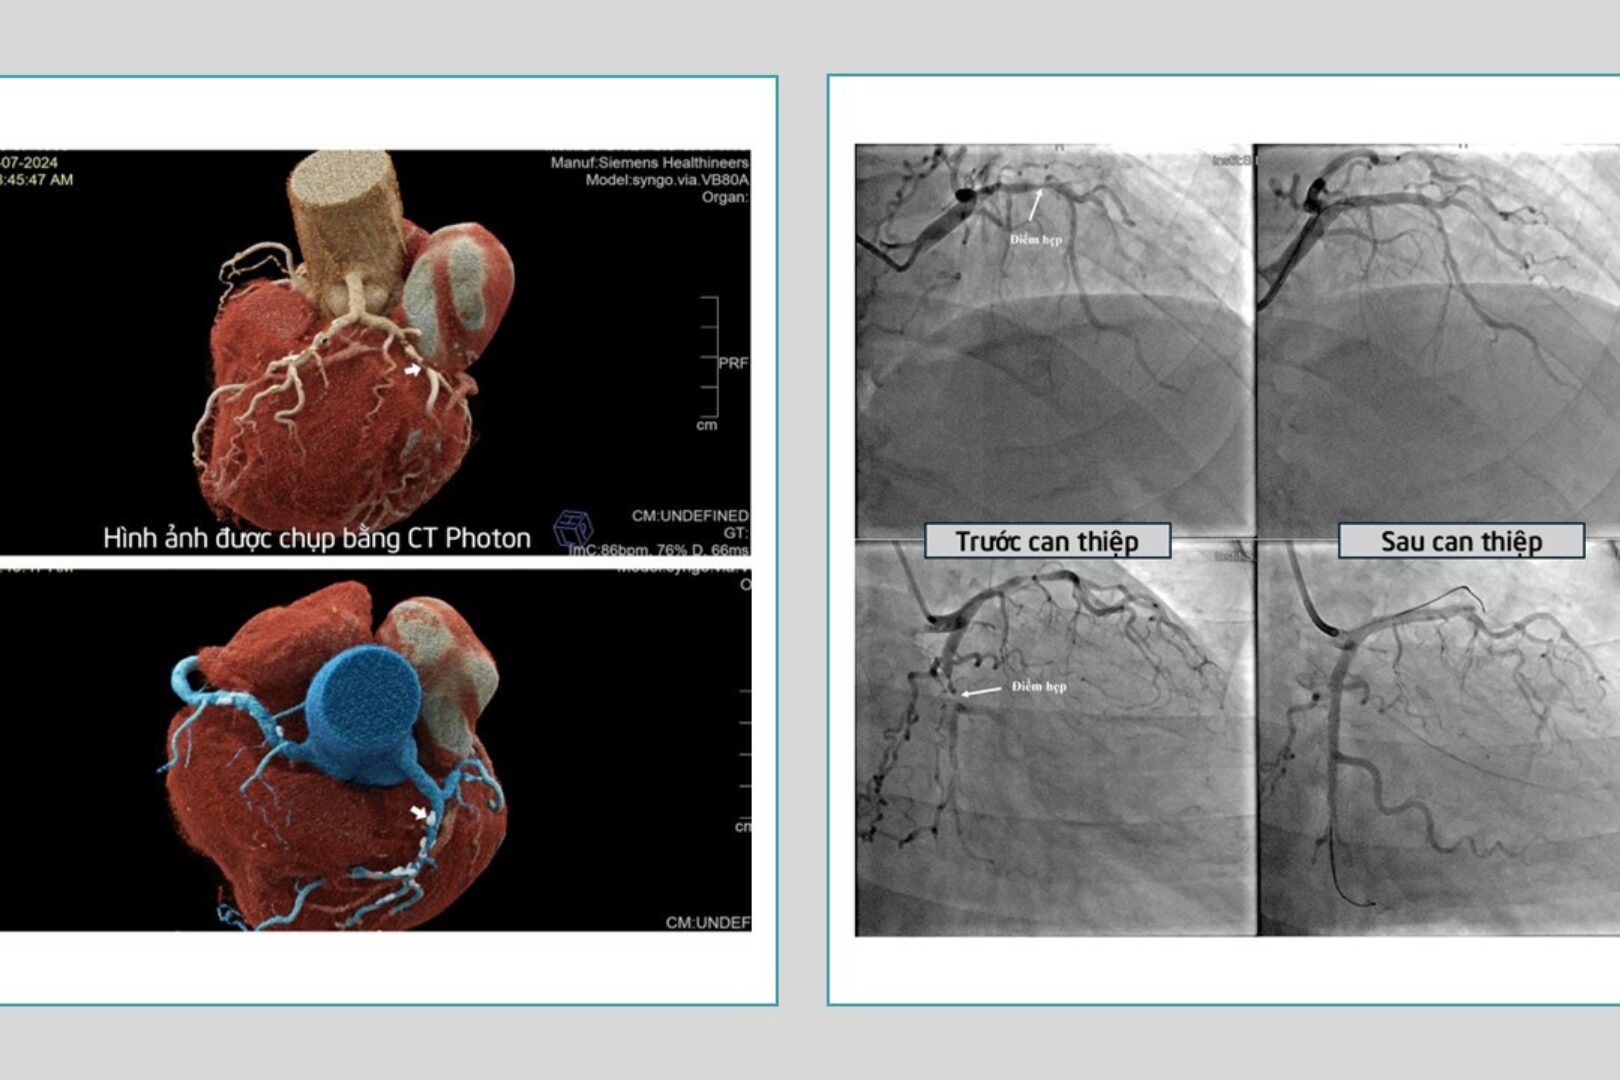

Hình ảnh vị trí mạch vành bị tắc và hẹp (Ảnh: BVCC)

Tại Bệnh viện Đa khoa Quốc tế S.I.S Cần Thơ, quan thăm khám kết hợp cận lâm sàng, các bác sĩ kết luận ông Y bị nhồi máu cơ tim cấp với men tim tăng, hình ảnh trên CT Photon cho thấy tắc nghẽn 2 nhánh mạch vành.

Sau khoảng 60 phút can thiệp, ê-kíp đã đặt thành công 2 stent ở 2 vị trí mạch vành đang bị hẹp nặng và tắc, giúp tái thông hoàn toàn mạch máu nuôi tim.

Tiếng chuông cảnh báo từ những triệu chứng bệnh mạch vành mơ hồ Qua trường hợp này, BS.CK1 Nguyễn Đức Chỉnh – Trưởng khoa Nội tổng hợp, Bệnh viện Đa khoa Quốc tế S.I.S Cần Thơ nhận định, những xét nghiệm thông thường như điện tim, siêu âm… rất khó để phát hiện được những trường hợp bệnh mạch vành khi biểu hiện triệu chứng chưa nặng nề. Đôi khi bệnh nhân chỉ có những triệu chứng tương đối mơ hồ như giảm khả năng gắng sức, hụt hơi nên dễ bị bỏ qua. Những bệnh nhân lớn tuổi, có tăng huyết áp, hút thuốc lá, uống rượu bia nhiều năm, rối loạn lipid máu, đái tháo đường… cần lưu ý khi có các triệu chứng mệt khi vận động thông thường, bị hụt hơi, khó thở, tức ngực, nhất là những trường hợp sau đặt stent mạch vành. BS.CK1 Nguyễn Đức Chỉnh cho biết thêm, phương pháp chụp CT Photon hiện nay là tối ưu nhất trong việc loại trừ bệnh động mạch vành nặng giảm được rủi ro dẫn đến nhồi máu cơ tim cấp có thể gây đột tử mà không có triệu chứng báo trước. |